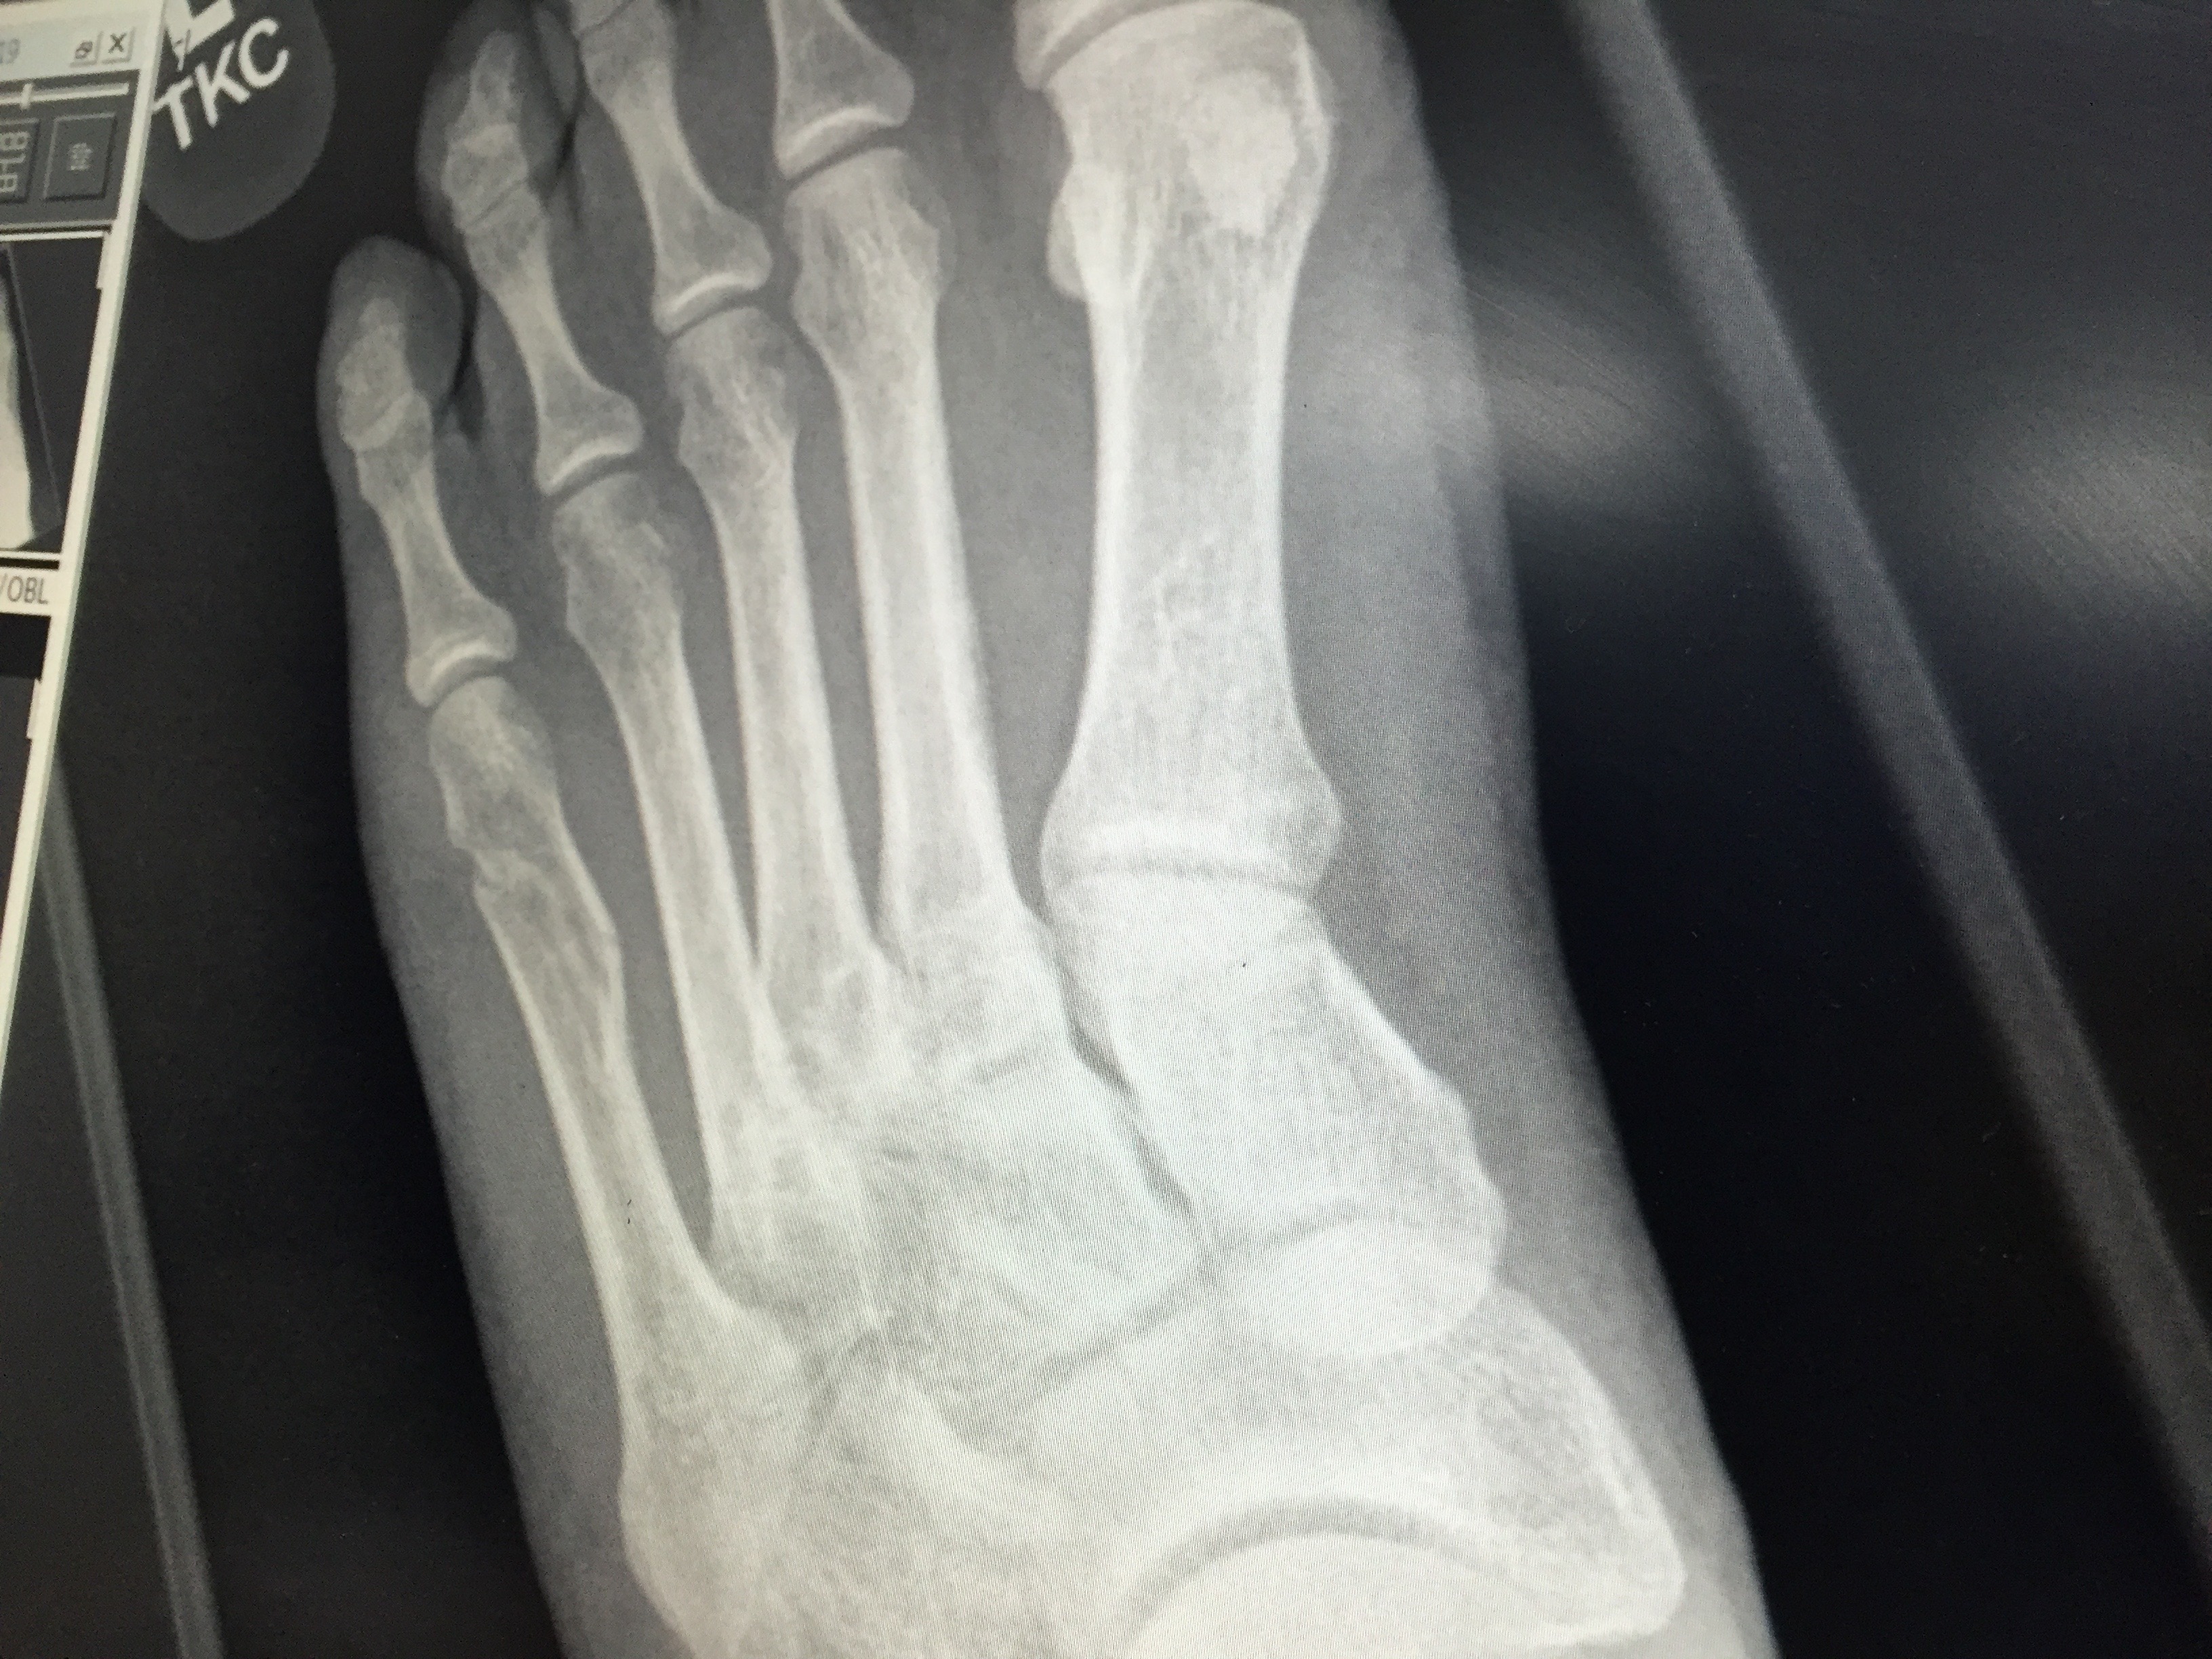

IMG_1475 (1) Published May 26, 2016 at 3264 × 2448 in Breaking my 5th Metatarsal Bone – Spiral Fracture How my bone has healed after 7 weeks